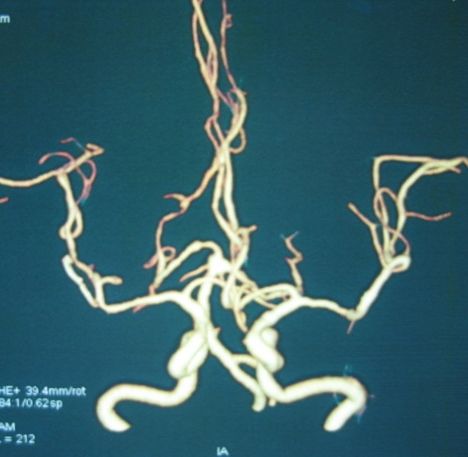

病例1、手术夹闭动脉瘤:男性,62岁,右侧大脑中动脉动脉瘤破裂出血,并形成脑内血肿。经过全科医生分析,动脉瘤位置浅,宽颈,而且形成了脑内血肿,栓塞相对较困难,决定施行动脉瘤手术夹闭+血肿清除术。3月14日,孟祥靖主任带领崔友强副主任医师、张霄川医师在手术室、麻醉科的配合下,顺利夹闭动脉瘤,经CTA复查,动脉瘤完全消失,大脑中动脉通畅,目前,患者已痊愈出院。

病例1:右侧大脑中动脉动脉瘤手术前、后,以及CT显示动脉瘤夹